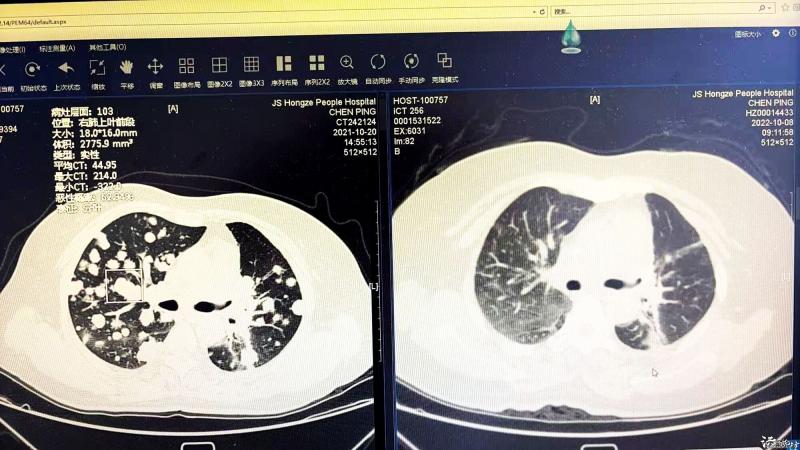

此后的两个多月,曹刚每天都会详细查看患者的各项指标,根据病情及时完善治疗方案。终于,奇迹再次降临,患者身上的癌细胞得到了有效缓解,精神状态也一天比一天好。从2021年的两肺广泛肺癌病灶,到如今的两肺病灶几乎完全消失,曹刚主任带领呼吸科团队用不放弃的精神不停地战胜着病魔。女孩回想起当初对曹刚主任的质疑态度,再看到如今母亲这么好的治疗效果,内心充满了愧疚,她含热泪对曹刚主任说:“对不起曹主任。若不是您的坚持与付出,我们真不敢想象现在会是什么样子。”